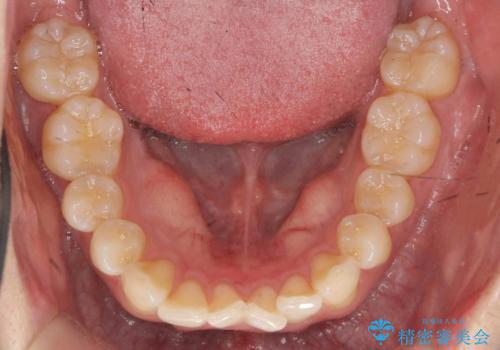

- 20代男性

- ワイヤー

- 10ヶ月

- 取り外しの必要なマウスピース矯正ではなくワイヤー矯正を希望され来院されました。

マウスピース矯正、ワイヤー矯正どちらの方法でも治療は可能ですが、ご要望の通りワイヤー矯正で歯の排列を行っていきます。